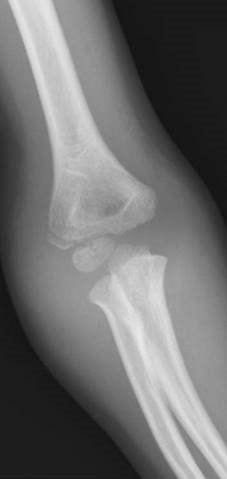

Can you describe the injury to me?

This is an AP radiograph of the right elbow showing a Monteggia fracture dislocation. I would like to see further views of the whole forearm as well as a lateral view of the elbow to determine the exact direction of dislocation of the radial head.

How do you classify these types of injury?

C lassifi cation of Monteggia fractures is using the Bado system and is determined by the direction of radial head dislocation:

1. Anterior 70โ€“85 %

2. Posterior (5 % ; more common in adults than children)

3. Lateral (15โ€“25 % )

4. Any: with associated radial shaft fracture (rare)

How would you manage this patient?

Management of this isolated injury can be divided into initial A&E management and defi nitive management. I would fi rst assess the patient in A&E giving some analgesia and taking a full history. On examination I would check the soft tissues for any evidence of open fracture or compartment syndrome as well as documenting carefully the distal neurovascular status. The posterior interosseus nerve is particularly at risk. This fracture dislocation needs to be reduced and fi xed urgently. I would organize for the patient to go to theatre when medically safe. In theatre I would use a direct approach to the ulna shaft utilizing the internervous plane between extensor carpi ulnaris (ECU) (posterior interosseous nerve, PIN) and fl exor carpi ulnaris (FCU) (ulnar nerve, UN). I would reduce the fracture under direct vision and then check with an image intensifi er whether the radial head had relocated. I would fi x this fracture with a 3.5-mm dynamic compression plate using AO principles.

You choose to open and reduce the ulna fracture under direct vision and fi x it with a dynamic compression plate. Tell me how this plate works.

Compression can be applied across the fracture in a number of diff erent ways. Firstly by pre-bending the plate; secondly by placing the screws eccentrically in the combihole to allow sliding compression at the fracture site; and thirdly by utilizing the compression device via a separately placed screw adjacent to the plate.

P ost-operatively I would protect the soft tissues in a backslab for 4 weeks to prevent late subluxation of radial head. The patient would then require physiotherapy to regain elbow motion.